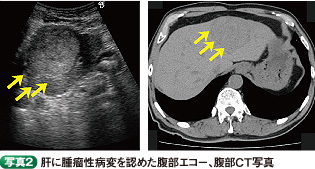

。また、腹部エコー・CTでは、肝左葉外側域に63×53×49mmの内部均一な腫瘤性病変が認められ、組織学的に肝細胞癌と診断された

。